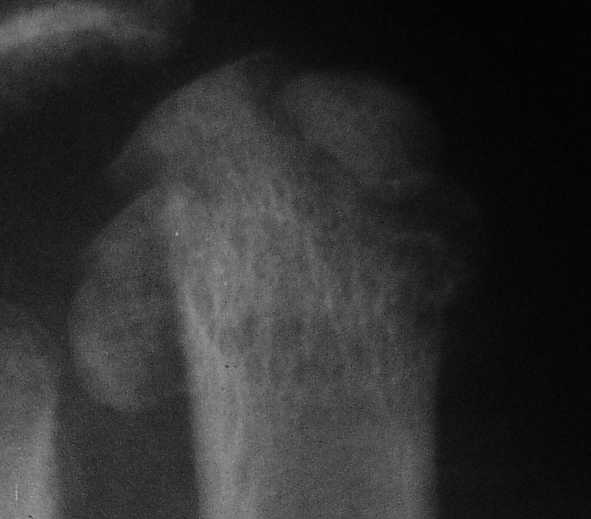

sa> 3 кстати, Вы перелом пкрвой плюсневой видите? В каком месте и на каком снимке?

Вот головка более прицельно.